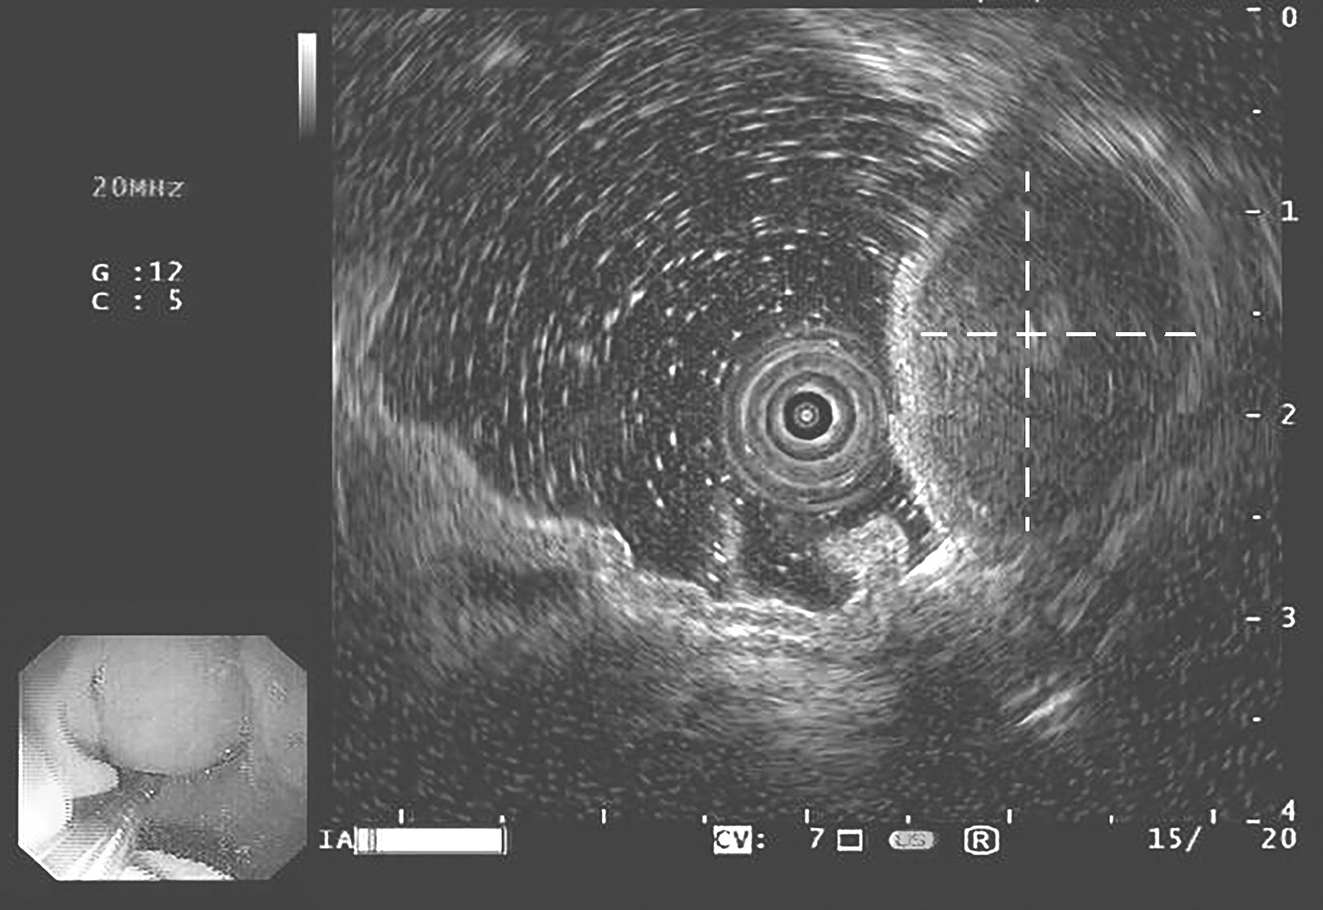

患者,女性,68岁,2016年10月因“腹痛1周”就诊于当地医院。行胃镜检查示:①胃底肿瘤;②糜烂性胃炎。当地医院给予抗炎和护胃等对症支持治疗。为求进一步治疗,患者于2016年11月至华中科技大学同济医学院附属协和医院胃肠外科门诊就诊,行超声胃镜检查示(图1):贲门大弯侧可见一隆起性病变,表面黏膜光滑,边界尚清,肿块内部回声均匀,病灶最大切面约2cm×2cm,包膜完整,起源于固有肌层,凸向腔内生长,胃肠间质瘤?门诊以“胃底占位性病变:胃肠间质瘤?”收治入院。

图1 超声胃镜检查